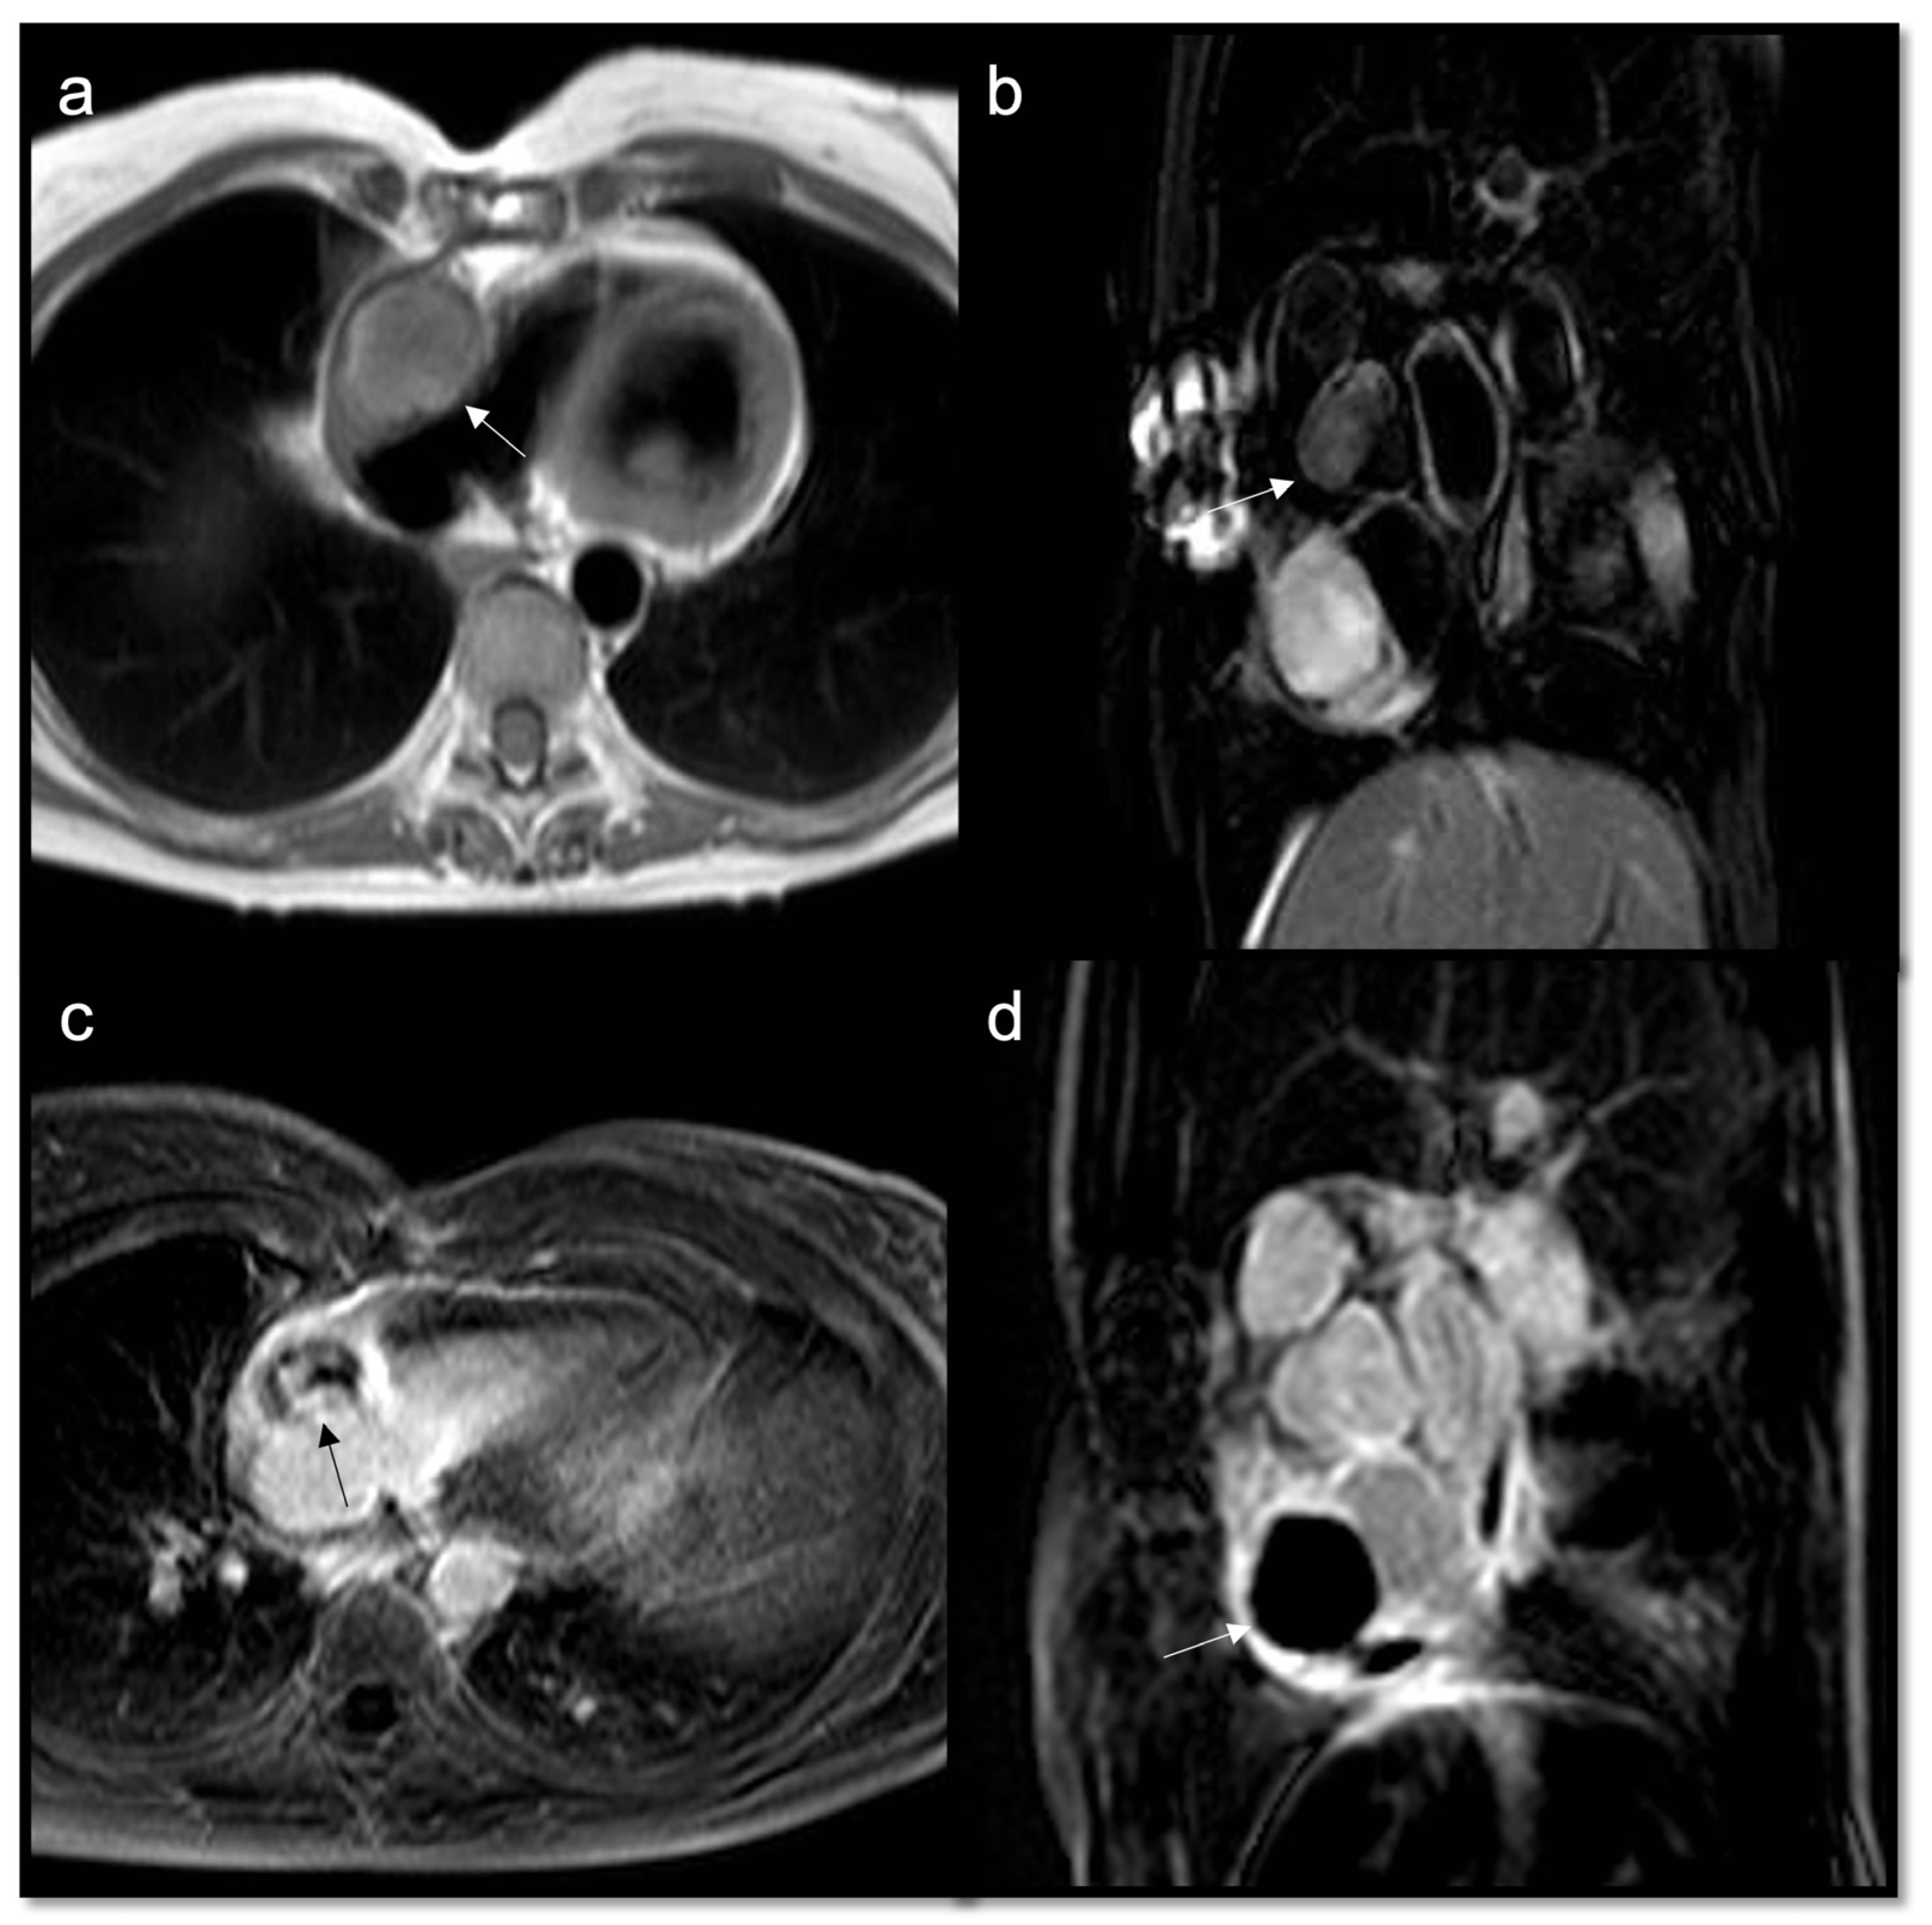

Figure 9.

Papillary fibroelastoma of the tricuspid valve (arrow) appears as a highly mobile, spherical pedunculate mass attached to the posterior tricuspid valve leaflet and on T1w images (a) it is homogeneous; no fatty content is found in T2w Fat Sat (b). LGE images demonstrate a hyperintense signal caused by fibroelastic tissue of the mass in 4CH and 2CH of the right ventricle (c,d). Approximately 80% occur concerning either the aortic or mitral valve, while tricuspid and pulmonary involvements are much rarer.

Figure 10.

Neuroendocrine lung tumor with left atrial metastasis due to contiguous spread (a); the atrial mass (arrow) has the same signal as the lung malignant tissue (arrow head) in axial T1w sequences (b), shows heterogeneous enhancement in EGE SA (c), and indicates a slight enhancement in LGE 4CH (d).

Figure 11.

Multiple epi- and intra-myocardial nodules (arrows) along the lateral wall of the left ventricle; subtle hyperintensity on T2w Fat Sat (a) that enhances in LGE (b) in a patient with thymoma.

Figure 12.

Heterogeneous right atrial mass (arrow) iso-hypointense in T1w and slightly hyperintense in T2w Fat Sat (a,b), with inhomogeneous enhancement in LGE axial acquisition (c), turned out to be an angiosarcoma. After multiple cycles of chemotherapy and radiotherapy, there was no perceptible enhancement in LGE SAX acquisition (d).

Figure 13.

Rhabdomyosarcoma (arrow) is hyperintense on T2-weighted images (a) and it shows contrast enhancement with regions of hypointensity due to central necrosis (b).